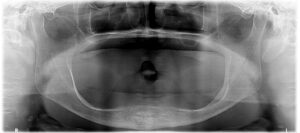

治療前 使用中の上下顎総入れ歯は、修理のつぎはぎ痕が多く存在しています。総入れ歯の土台となるあごの骨の吸収量が多く、また噛み合わせが左にズレていることから、入れ歯が吸着してよく噛めることがは難しい状態でした。

1. 初診相談

お口の中の診査結果から、とくに下あごの解剖学的状態が入れ歯の吸着を得るためには不利であることがわかりました。また、両側顎関節のCT像からとくに左側顎関節の形態異常を認め、あごの動き方に問題がありました。現状での生活の質(QOL)も70満点中35点とかなり障害されています。患者さんのご要望に応えて入れ歯で機能させるには難症例であることから、最終的な入れ歯を装着する前にリハビリテーション目的で治療用義歯を装着してもらい、これを使用してもらいながら、あごの解剖学的条件の改善と機能の改善を図ることとしました。